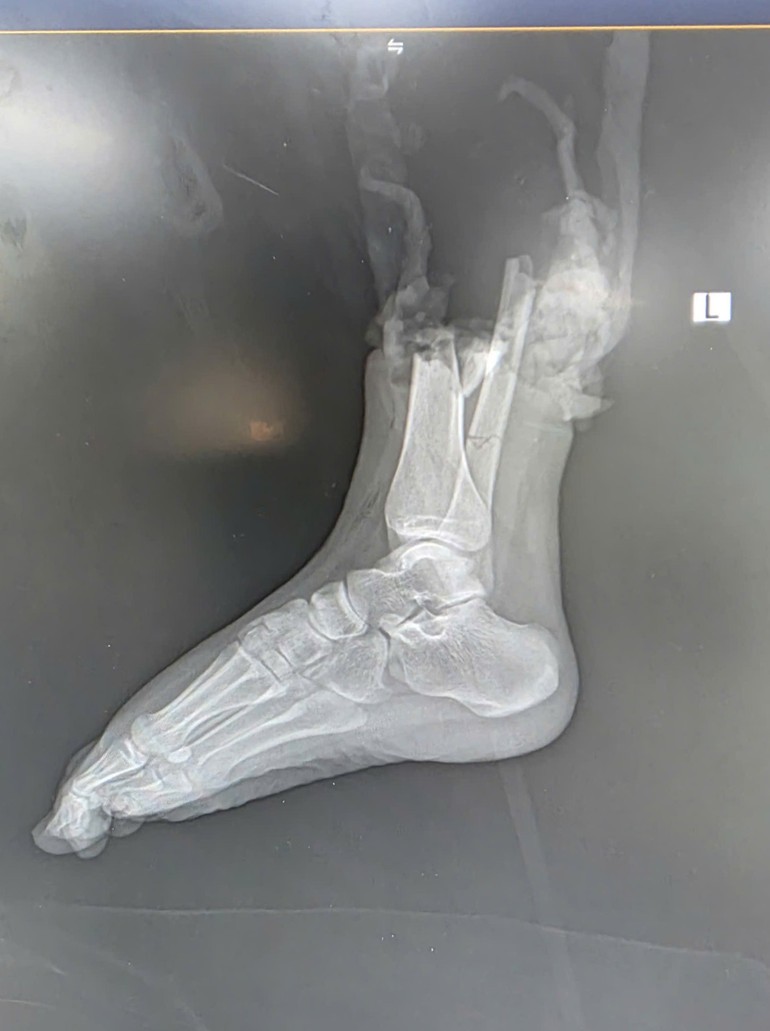

Hình ảnh tổn thương trên CT.